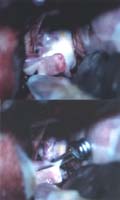

<¼ö¼ú

Àå¸é> <¼ö¼ú

ÈÄ>

¼ö¼ú

ÈÄ µ¿¸Æ·ù°¡ º¸ÀÌÁö ¾ÊÀ¸¸ç µ¿¸Æ·ù °æºÎ¿¡

Ŭ¸³ÀÌ µé¾î°¡ ÀÖ´Â °ÍÀÌ º¸À̰í

ÀÖ´Ù.